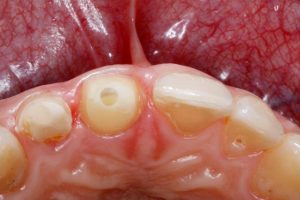

Die Basis für eine perfekte Abformung ist ein eröffneter und trockener Sulkus. Mit der VOCO Retraction Paste, die direkt aus dem Caps in den Sulkus appliziert wird, bringt der Cuxhavener Hersteller jetzt ein Produkt für die effektive temporäre Eröffnung und Trockenlegung des Sulkus auf den Markt, das gleichzeitig die ideale Ergänzung zum Präzisionsabformmaterial V-Posil darstellt. VOCO Retraction Paste bietet die Voraussetzung für eine erfolgreiche klassische oder auch digitale Präzisionsabformung sowie für Kavitätenpräparationen bei Klasse II und V Füllungen aber auch für definitives und temporäres Zementieren von Restaurationen.

Dabei überzeugt die Retraktionspaste nicht nur im Ergebnis, sondern auch mit ihrem Handling: So gibt die Farbe einen guten Kontrast zur Gingiva, was insbesondere die Arbeit an schwer einsehbaren Stellen erleichtert. Dank der sehr schmalen und leicht biegsamen Kanüle lässt sich das Material sowohl gut dosieren als auch applizieren. Hierbei ist die Paste leicht auszudrücken und punktet anschließend mit einer sehr guten Fließviskosität bei gleichzeitiger Standfestigkeit zur Eröffnung des Sulkus.Bei der Applikation füllt die adstringierend wirkende, aluminiumchlorid haltige Paste temporär den Sulkus, stoppt etwaige Blutungen und verdrängt Feuchtigkeit.

Die Paste kann als Alternative oder in Kombination z.B. mit Retraktionsfäden verwendet werden. Dabei ist die Nutzung klassisch oder digital mit Intraoralscanner möglich. Weichgewebsmanagement ist auch für entsprechende Füllungen der Klassen II und V sowie beim definitiven und temporären Zementieren von Restaurationen oft der Schlüssel zum Erfolg, insbesondere bei der Adhäsiv-Technik mit wenig feuchtigkeitstoleranten Produkten.